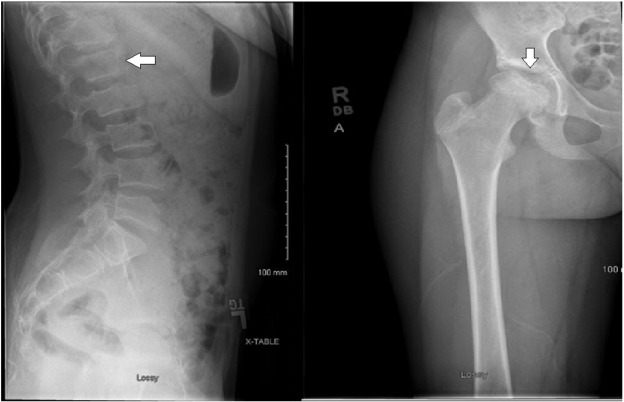

The patient is a now 15-year-old Caucasian female with normal early development, but postnatal onset of short stature with diminished growth velocity, although she did have an increase in growth velocity during her pubertal growth spurt of 9 cm between ages 12.85–13.80 years, which slowed to 5.5 cm between 13.80 years and reaching final adult height of 147.5 cm at 15.0 years (Fig. 1 ). Her adult height is 1.5 standard deviations above the mean for adult females with MPS IVA based on height data published by Montano and colleagues in 2007 [8] . This patient has had no cognitive or educational concerns and is a good student in school. She has above average intelligence and is quite social. She was in good health until eight months before initial presentation when she was diagnosed with type I diabetes and started on a typical insulin regimen. She was also found to have thyroid peroxidase and thyroglobulin antibodies, but has remained clinically euthyroid. Prior to presentation, the patient had been involved successfully with a competitive swimming team, but she began to experience lower back pain and right hip pain. Initially pain occurred with activity, but eventually was present even at rest. Radiography performed at that time showed irregularity of the right proximal femoral epiphysis along the subchondral surface, which was felt to be consistent with avascular necrosis of the femoral head. Similar features were found to a lesser degree on the left femoral head. Irregularity in the vertebral bodies was also noted, but without characteristic beaking of the anterior vertebral bodies. Repeat radiography at the time of presentation confirmed irregularity of the vertebral bodies, which was initially concerning for compression fracture, but later felt to represent platyspondyly (Fig. 2 ).

Fig. 2

Fig. 2.

Lateral lumbar spine radiograph showing end-plate irregularity and platyspondyly denoted by arrow. Right hip film showing somewhat shallow and sclerotic acetabulum with significant femoral head irregularity also denoted by arrow.